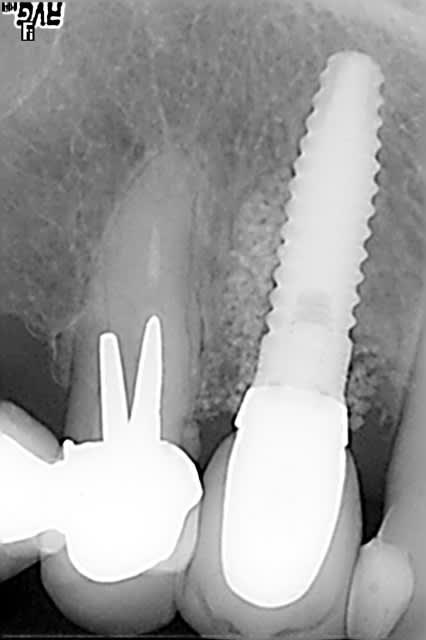

pour candide:

je te propose ce cas que j'ai achevé il y a 2 mois; tu verras que la notion de limite est variable, sauf celle du blocage primaire, d'où cette proposition de mise en esthétique uniquement avec un bon blocage primaire;

dans le cas présenté, je n'ai bien évidemment pas fait de mise en esthétique, j'ai simplement mis une PAP d'une dent, puisque la 14 est une CCM où je ne pouvais pas faire de collage

j'ai mis du ß TCP sans membrane, j'ai eu une très légère récession gingivale que l'utilisation des TBR Zircone autorise sans soucis avec un sourire non gingival

la pose a été faite 6 mois plus tard

la dernière radio est à 6 mois post op, il y a eu une petite inflammation distale qui m'a fait perdre un peu de hauteur, provoquée par un grain de TCP qui est resté bloqué en surface pendant les vacances cet été; le PBI est revenu à 0 depuis